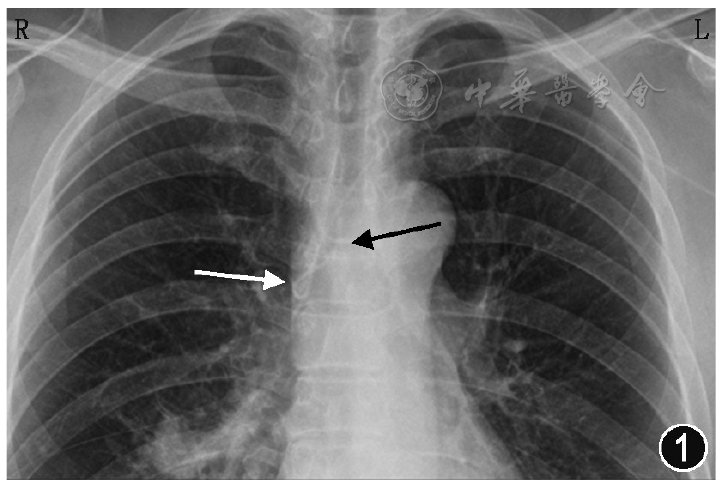

患者返回血管通道中心,重新对穿刺部位导管和皮肤进行消毒,根据胸部X线片上电子标尺测量导管打折长度约2.5 cm,故将导管从静脉中拔出3 cm,然后重新送入导管。连接科曼C100心电定位仪,4个电极片分别贴于右锁骨下(RA)、左锁骨下(LA)、左下(LL)腹部、右下(RL)腹部,屏幕抓取二导联心电波形原始资料记录患者基础心电图,取下RA导联,将无菌导联线鳄鱼夹一端夹在20 ml注射器注射针头针柄上,一端连接心电定位仪,采用生理盐水引导腔内心电图定位方法,心电图显示P波高尖,P波振幅等于QRS波振幅的1/2(图2),提示导管尖端位于SVC中、下三分之一。随后拍摄的CXR显示导管尖端位于SVC中段,导管末端仍然反折成L型(图3)。故进行第二次导管尖端位置调整,在心电图定位下,拔出部分导管,直到高P波消失。然后轻柔缓慢将导管再次送入血管至导管0刻度位置,观察P波振幅从正常到高尖,但未观察到负向P波改变,继续将导管0刻度后1 cm长度导管送入血管,观察到高尖P波前有一个负向小P波,即双向P波(图4)。最后,将导管拔出1 cm,导管外露0刻度。再次拍摄的CXR显示导管尖端位于SVC的下三分之一处(图5)。

在ECG定位下,拔出部分导管,直到高P波消失。然后轻柔缓慢地将导管再次送入血管至导管0刻度位置,观察P波振幅从正常到高尖,但未观察到负向P波改变,继续将导管0刻度后1 cm长度导管送入血管,观察到高尖P波前有一个负向小P波,即双向P波。最后,将导管拔出1 cm,导管外露0刻度。再次拍摄的CXR显示导管尖端位于SVC的下三分之一处。